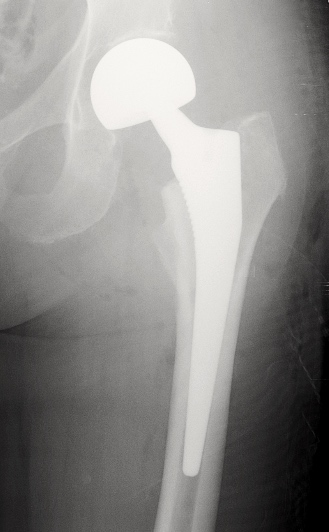

C. PTH avec polyéthylène et tige cimentée